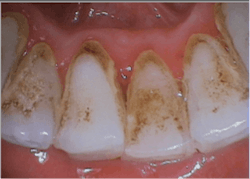

- Air polishing removes biofilm, stain, and immature dental calculus.

- Piezoelectric ultrasonic removes firmly established dental calculus.

By air polishing first, I improve my patient’s debridement experience by decreasing the time of use with high-pitch frequency machines like the ultrasonic and scraping sounds with hand instruments. There are many studies reporting improved patient comfort during subgingival debridement with air polishing than compared to other forms of instrumentation.1-5